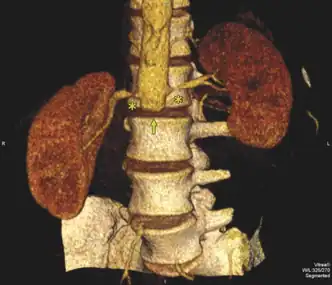

Diagram of renal artery stenosis

Renal artery stenosis (RAS) is the narrowing of one or both of the arteries to the kidneys.[3] Early on there are typically no symptoms, while later high blood pressure or kidney problems may occur.[3] The blood pressure may be difficult to treat.[2] Complications may include chronic kidney disease, stroke, and coronary artery disease.[3]

About 90% of cases are due to atherosclerosis.[3] Other causes include fibromuscular dysplasia, vasculitis, AAA, and arterial dissection.[3][2] Risk factors for atherosclerosis include high cholesterol, smoking, diabetes, high blood pressure, obesity, inactivity, and family history.[3] Diagnosis is generally by ultrasound or CT scan.[2]

Diagnosis

The diagnosis of renal artery stenosis can use many techniques to determine if the condition is present, a clinical prediction rule is available to guide diagnosis.[10]